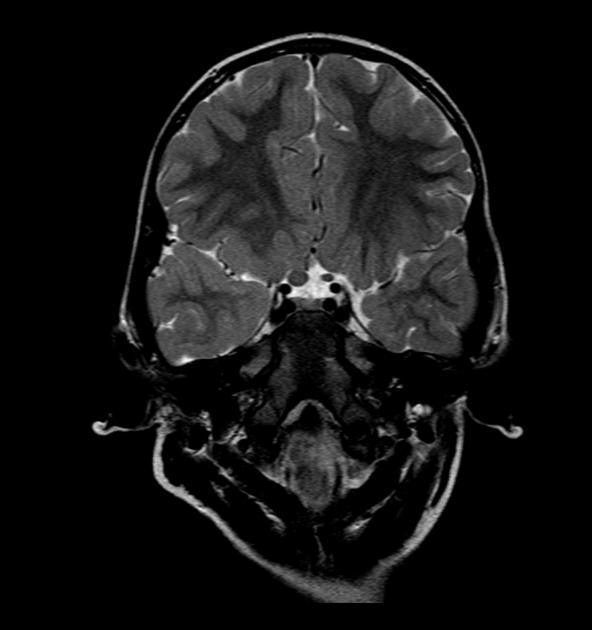

案例七

基本病史:2 岁女孩,摇头,双侧眼球震颤一年余。

图 7 MRI 检查轴位 T2WI 及 T1WI 强化序列显示双侧视神经肿胀呈长 T2 信号,强化呈明显强化,累及视交叉及颅内脑组织